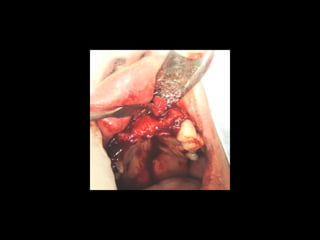

AmeloblastomaAmeloblastoma

Ameloblastoma

Trismus importante debido a queTrismus importante debido a que

El tumor ya rompió el hueso com-El tumor ya rompió el hueso com-

Pacto de la cara interna de laPacto de la cara interna de la

Mandíbula y empezó a tomar elMandíbula y empezó a tomar el

Músculo pterigoideo interno.Músculo pterigoideo interno.